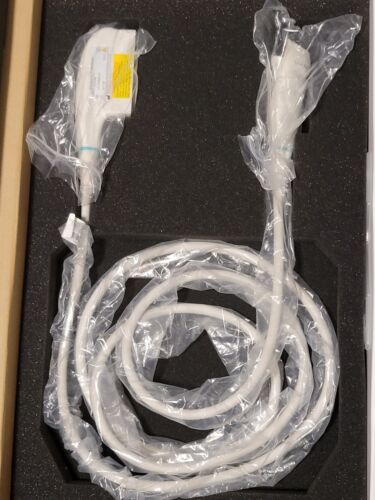

Mindray L14-6Ns Linear Ultrasound Transducer Probe (New)

Regular price $1,999.00 USDRegular priceUnit price / per -

Mindray L14-6Ns Linear Ultrasound Transducer Probe (New)

Regular price $2,499.00 USDRegular priceUnit price / per -